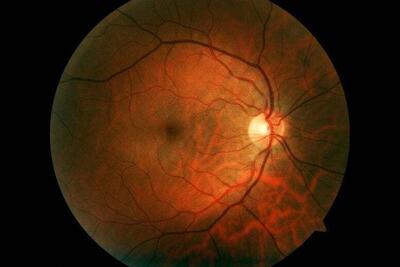

با افتتاح و بهرهبرداری از دستگاه پتاسکن (PET Scan) در هرمزگان، این استان به جمع معدود استانهای کشور پیوست که این خدمت تخصصی تصویربرداری پزشکی را با تعرفه دولتی به بیماران ارائه میدهند.

کردستان در ردیف ۶ استان برخوردار از دستگاه پتاسکن( تشخیص سرطان)

رئیس دپارتمان پزشکی هستهای پزشکی هستهای و تصویربرداری بیمارستان کوثر سنندج گفت: کردستان ششمین استاد کشور در دریافت دستگاه pet scan پیشرفته از نوع ۲۰۲۱ است که نشان از اهمیت و توجه به تجهیزات پزشکی پیشرفته در استان است.

آمادگی های لازم برای اسکن هسته ای قلب

اسکن هسته ای قلب یکی از روش های پیشرفته تصویربرداری برای شناسایی مشکلات قلبی است. این مطلب به نکات مهمی جهت آمادگی اسکن هسته ای قلب اشاره دارد.